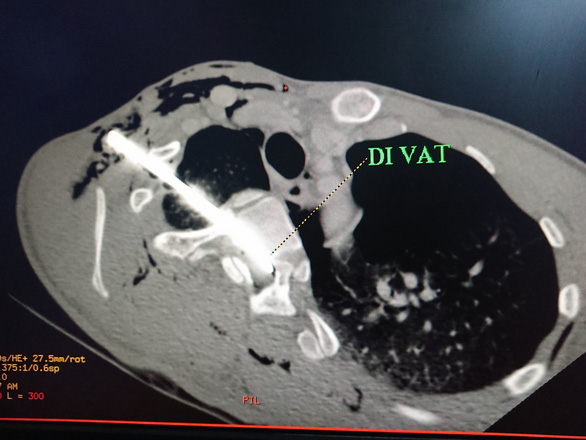

Bệnh nhân được thực hiện các xét nghiệm, kết quả X-quang tim phổi thẳng cho thấy: một dị vật cản quang từ vùng cổ phải xuyên xuống đoạn gian đốt sống D3/D4, tràn khí màng phổi hai bên.

Kết quả chụp CT64 lát cột sống cổ không cản quang cho thấy: dị vật kim loại đường kính 0.5cm dài 10cm xuyên từ vùng cổ phải đến khe gian đốt sống D3/D4 chèn vào mặt trước ống tủy, tụ khí dưới da vùng cổ ngực hai bên, tràn khí và ít dịch màng phổi phải, tràn khí màng phổi trái.